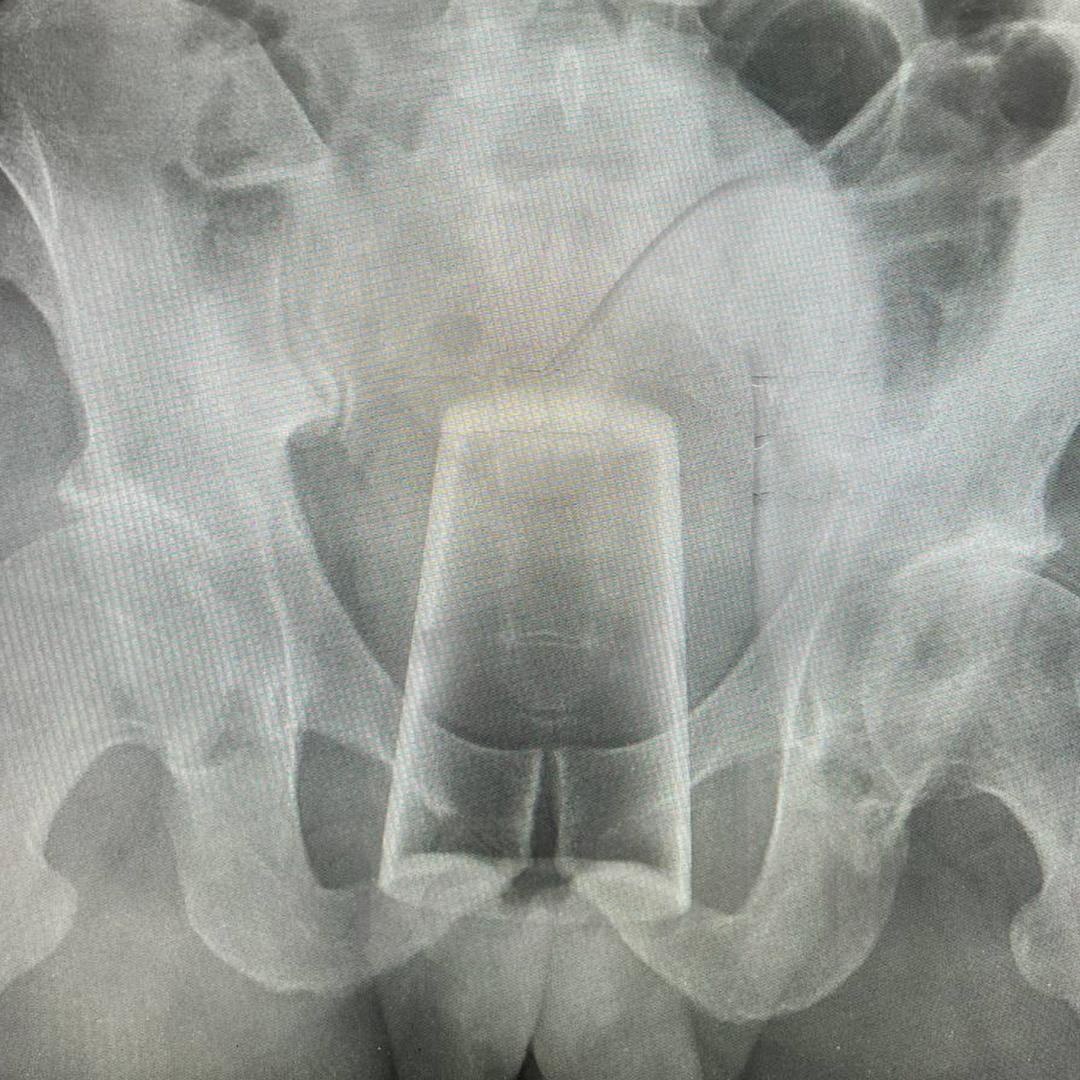

A Russian man celebrating Defender of the Fatherland Day somehow managed to get a glass stuck in his backside

According to him, he slipped and accidentally fell onto the glass. How that was even possible, why he wasn't wearing pants, and how the glass didn't break -- remain unclear.

Attempts to remove the object on his own were unsuccessful, so he had to call medics.

NATO je kriv!